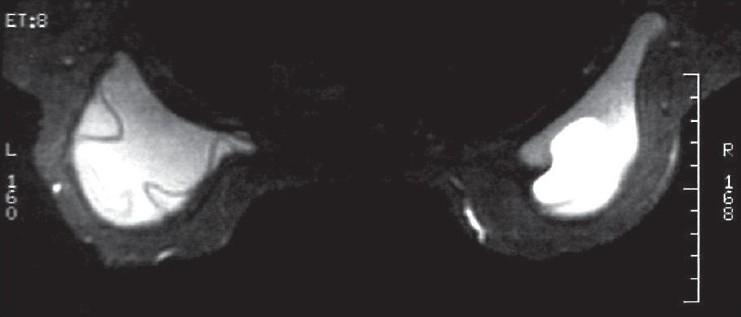

We report a case involving a 45-year-old woman, who presented with an axillary mass 10 years after bilateral cosmetic augmentation mammaplasty. A lump was detected in the left axilla, and subsequent mammography and magnetic resonance imaging demonstrated intracapsular rupture of the left breast prosthesis. An excisional biopsy of the left axillary lesion and replacement of the ruptured implant was performed. Histological analysis showed that the axillary lump was lymph nodes containing large amounts of silicone. Silicone lymphadenopathy is an obscure complication of procedures involving the use of silicone. It is thought to occur following the transit of silicone droplets from breast implants to lymph nodes by macrophages and should always be considered as a differential diagnosis in patients in whom silicone prostheses are present.

我们报告了一例病例,患者为一名45岁女性,在双侧隆胸整形术后10年出现腋窝肿块。在左腋窝发现一个肿块,随后的乳房X线摄影和磁共振成像显示左乳房假体包膜内破裂。对左腋窝病变进行了切除活检,并更换了破裂的植入物。组织学分析表明,腋窝肿块是含有大量硅胶的淋巴结。硅胶淋巴结病是涉及使用硅胶的手术中一种罕见的并发症。它被认为是在硅胶滴通过巨噬细胞从乳房植入物转移到淋巴结后发生的,对于存在硅胶假体的患者,应始终将其视为鉴别诊断。